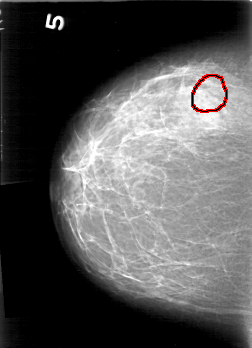

D_4167_1.RIGHT_MLO

RIGHT_MLO LINES 5266 PIXELS_PER_LINE 3511 BITS_PER_PIXEL 12 RESOLUTION 43.5 OVERLAY

FILE: D_4167_1.RIGHT_MLO.OVERLAY

TOTAL_ABNORMALITIES 1

ABNORMALITY 1

LESION_TYPE CALCIFICATION TYPE PUNCTATE-AMORPHOUS DISTRIBUTION CLUSTERED

ASSESSMENT 0

SUBTLETY 2

PATHOLOGY BENIGN

TOTAL_OUTLINES 1

BOUNDARY